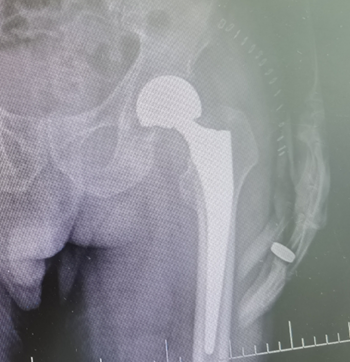

(术前)                          (术后)

在详细完善手术方案和做足了风险评估后,经得患者家属同意后,邓颂波及其团队一致决定采取手术治疗方案。在麻醉科的配合下,邓主任带领团队凭借多年经验,为老大爷顺利完成“左侧人工股骨头置换术”,术后在医护人员悉心照顾下,身体恢复良好,术后三天已能下床走路。